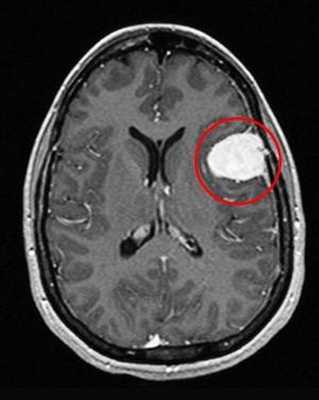

Перед вами - два снимка, сделанных в одном режиме. Снимок снизу - норма. Какое заболевание, в таком случае, есть на верхнем снимке? Чтобы понять это, нужно сравнить эти изображения. Явно видно отличие - на верхнем снимке в правой части головного мозга есть новообразование. Разница еще заметнее, если сравнить левую и правую части того же снимка.

Отметим его красной окружностью. Визуально оно представляет собой узел, неоднородный по окраске и отличающийся от серого и белого вещества головного мозга. В таких случаях, чтобы точно определить границы опухоли и определить её тип исследование повторяют с контрастом. Введение контрастного препарата в кровь через локтевую вену приводит к накоплению контрастного вещества в тканях опухоли - нормальные здоровые ткани его практически не накапливают. И мы получаем следующую картину, показанную на рисунке справа. Яркая окраска опухоли соответствует накопленному контрасту - теперь можно не только сказать, где опухоль, но и примерно определить, что это доброкачественная опухоль, так как она имеет четкие границы (злокачественные опухоли прорастают окружающие ткани, из-за чего границы будут размытыми и не такими четкими).